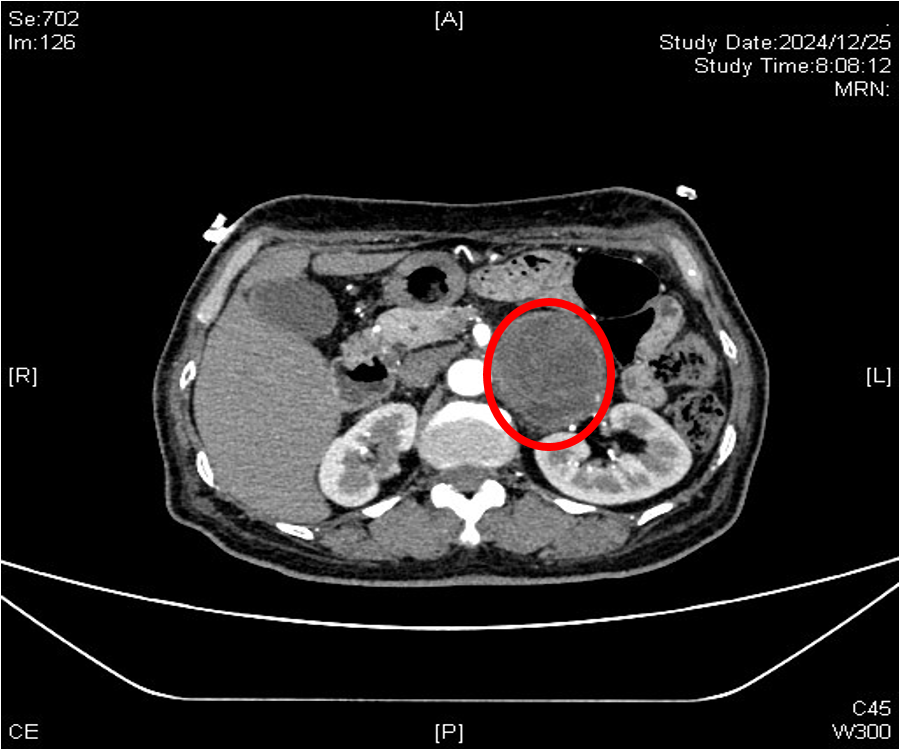

患者左侧巨大腹膜后肿瘤

患者李大妈患有一个直径近7厘米的巨大腹膜后肿瘤,肿瘤紧邻肾门血管、腹主动脉、胰腺及肠道等重要器官组织,边界模糊,加之她既往有高血压、糖尿病和房颤病史,身体基本情况较差,给治疗带来了难度。李大妈辗转多家医院就诊,最终来到青大附院泌尿外科平度病区。